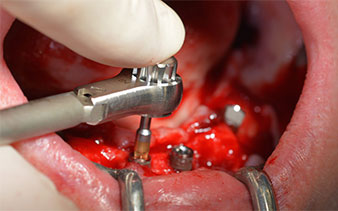

The surgical protocol for the implants employed (SKY, bredent medical) specifies a speed of 1,200 rpm for the pilot drilling (Fig. 7 - 9).

This corresponds to the next preset position in the Implantmed. Here we see the W&H contra-angle handpiece being held at a 45° angle to mesiocaudal in the region of 45 in order to preserve the mental nerve. The mental foramen is used as the anatomic reference for all drilling in this region. The subsequent holes were drilled at a reduced speed of 300 rpm (Fig. 10 and 11).